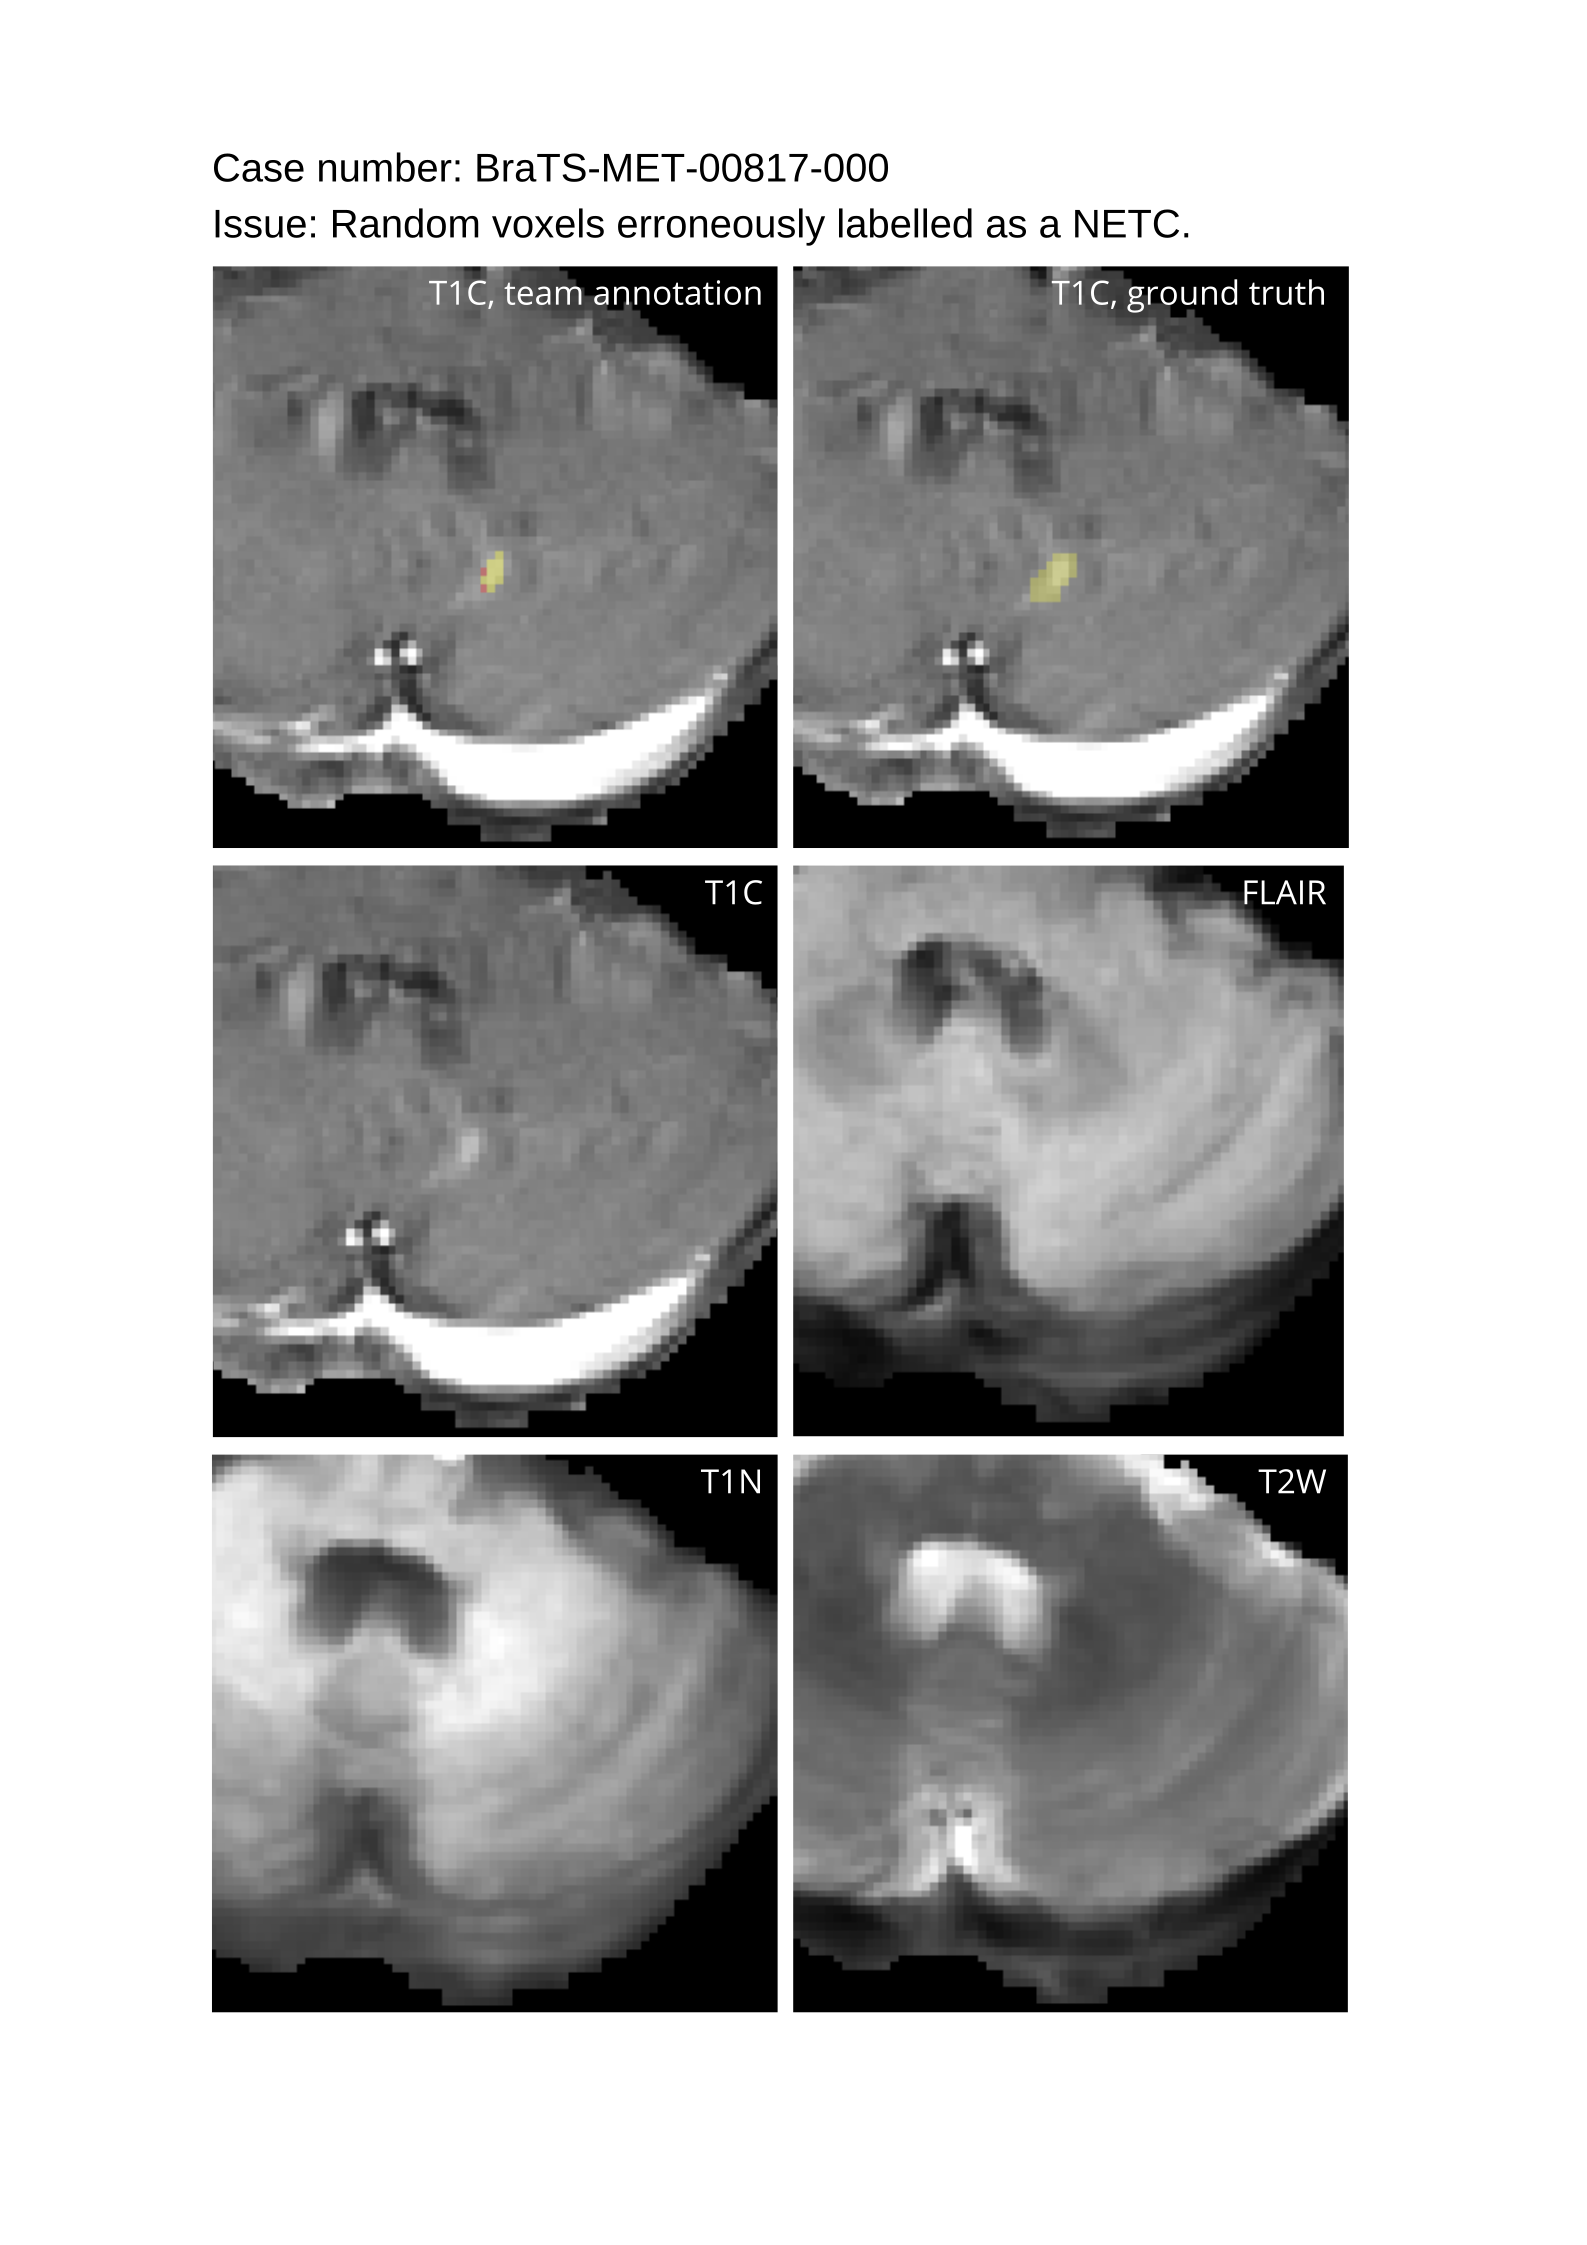

Approvers reviewed the volunteer annotations and either approved the case or returned it to students for re-annotation. Additionally, a QC process was implemented, which included removing all random voxels and any voxels outside the brain mask, ensuring all images had the same parameters (space, orientation, and origin) as the SRI24 atlas, and verifying the presence of all segmentations and segmentation masks are in the folder with original NIfTI images.

4.9 Common Errors of Automated Segmentations

Based on observations from previous BraTS challenges, common errors in automated segmentations were identified. The most typical errors in the current challenge included:

1. 1.

Automated algorithms missing small metastases. Enhancing metastasis was fused using the minority voting algorithm to aggregate all enhancing tumor voxels identified by the three algorithms. However, many small metastases were missed and were manually segmented by neuroradiology attendings.

2. 2.

Segmentation of white matter changes from microvascular disease. Peritumoral edema segmentations were checked by neuroradiology attendings and modified.

3. 3.

The segmentation of non-enhancing lesions that have intrinsic T1 hyperintensity. Voxels with intrinsic T1 hyperintensity were manually removed from ET segmentations.

These insights led to specific adjustments in the annotation process to enhance accuracy.